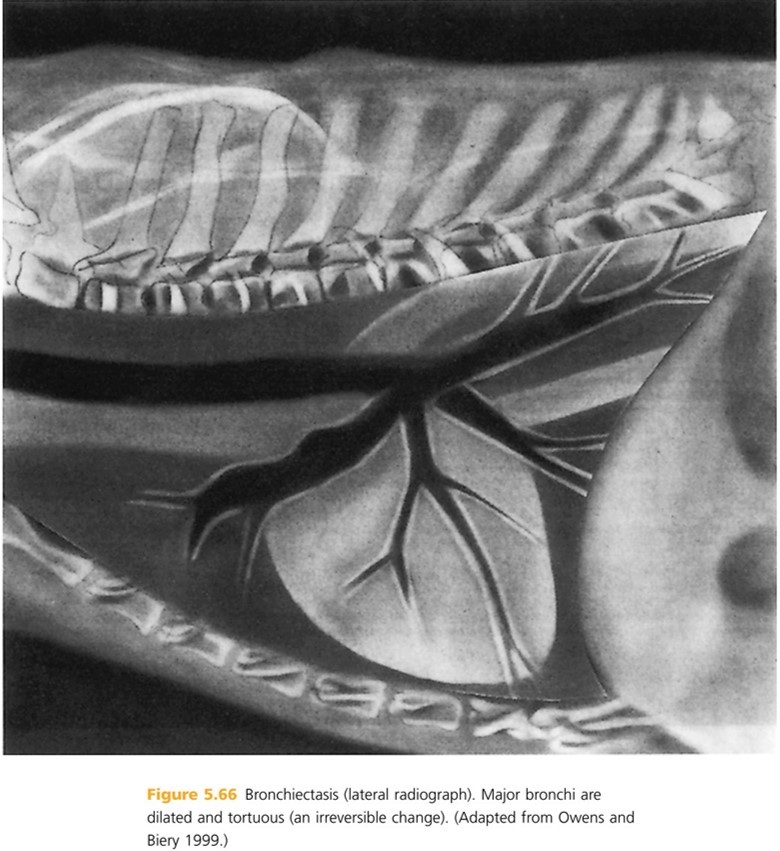

Outer bronchial margins may become indistinct due to disease in adjacent lung parenchyma or peribronchial infiltrates which is called ____ ____. Vascular margins usually remain sharp and well defined if lung dz is confined to ____. Bronchi with enlarged diameters and irregular shapes (bronchiectasis) typically result from ____ _____.

Peribronchial cuffing, bronchi, chronic inflammation

Definition of Bronchiectasis is:

Abnormal, irreversible, dialation of bronchi. It is uncommon in dogs and rare in cats (American Cocker Spaniel and Siamese cat may have higher incidence). Most often reported in middle-aged and older animals, but can happen at any age.

Acquired bronchiectasis results from _____ _____.

chronic inflammation